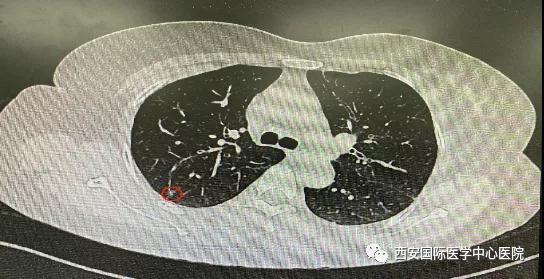

日前,西安國(guó)際醫(yī)學(xué)中心醫(yī)院胸科醫(yī)院胸外科二病區(qū)成功開(kāi)展LungPro全肺導(dǎo)航下經(jīng)支氣管鏡注入亞甲藍(lán)染色劑標(biāo)記結(jié)節(jié)位置,行精準(zhǔn)肺段切除術(shù),成為西北地區(qū)首例“Lung Pro全肺診療導(dǎo)航系統(tǒng)聯(lián)合單孔胸腔鏡下右肺上葉后段切除術(shù)”,填補(bǔ)了西北地……